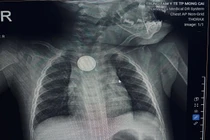

Hình ảnh dị vật là pin cúc áo trong thực quản trẻ. Ảnh: Bệnh viện Nhi Hải Phòng

Trung tâm Y tế Móng Cái (Quảng Ninh) vừa tiếp nhận cấp cứu bệnh nhi B.M.K. (11 tháng tuổi) nhập viện trong tình trạng nôn nhiều, quấy khóc dữ dội. Qua thăm khám và chụp X-quang, các bác sĩ phát hiện dị vật kim loại hình tròn mắc kẹt tại thực quản.

Bệnh nhi được chỉ định nội soi cấp cứu, phát hiện dị vật là một viên pin cúc áo. Các bác sĩ nhanh chóng lấy dị vật ra an toàn, tuy nhiên niêm mạc thực quản của trẻ đã bị tổn thương do phản ứng ăn mòn điện - hóa học. Hiện bệnh nhi đang được điều trị tích cực và theo dõi biến chứng.